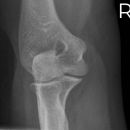

Ellenbogen seitlich

Patient sitzt seitlich am Tisch, Oberarm und Unterarm auf Schulterhöhe waagerecht aufliegend, Gelenk im Winkel von 90° gebeugt, Unterarm liegt ulnar auf, Daumen zeigt nach oben bei streng seitlicher Handstellung, Unterarm evtl. unterpolstern.

Senkrecht auf Gelenk- und Filmmitte.

Weitgehend freie Projektion des Radiusköpfchens, das sich als Oval abzeichnet, lediglich vom Processus coronoideus anteilig überlagert

Ellenbogengelenk vollständig seitlich orthograd abgebildet. Humeroulnar Gelenkspalt einsehbar. Humeruskondylen müssen sich decken, das Radiusköpfchen soll gut beurteilbar sein.